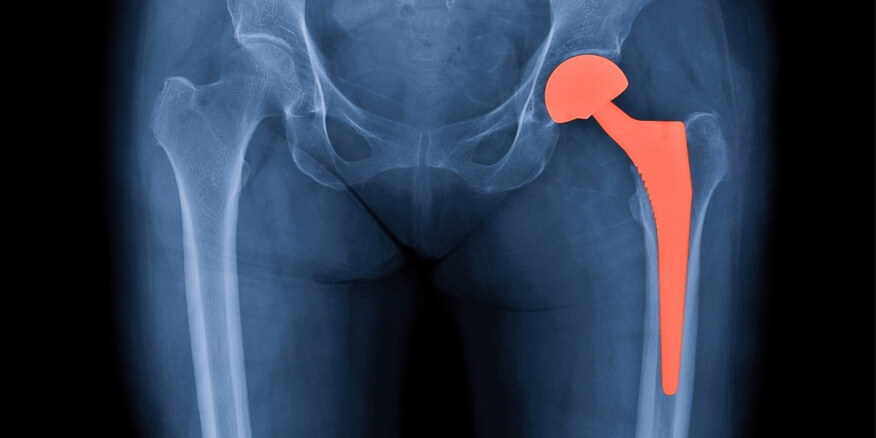

الكسور بعد تركيب المفاصل الصناعية: الأسباب والعلاج والوقاية

تركيب المفاصل الصناعية إنجاز طبي أعاد الأمل لكثير من الحالات المرضية المتقدمة ولكن لم يخلو التعافي من المضاعفات…